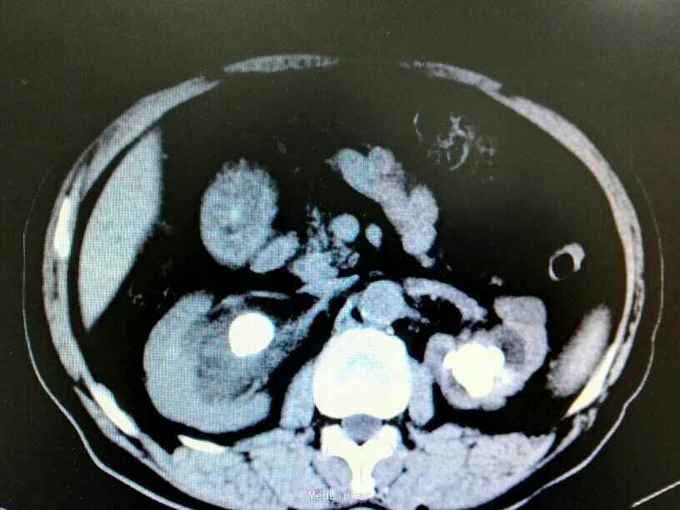

双肾铸型结石伴左肾萎缩一例

72岁男性,因“体检发现双肾结石1月”。既往10年前因双肾结石行双侧肾盂切开取石术(具体不详)。4年前因右肾输尿管结石行右侧输尿管碎石术。

双肾区叩痛。尿常规白细胞1500个/ul,两次尿培养阴性。左肾GFR15右侧38.9。

双肾铸型结石 左肾萎缩,尿路感染,双肾盂切开取石术后,BPH。经抗感染等治疗后,现在尿常规白细胞395.4个/ul。